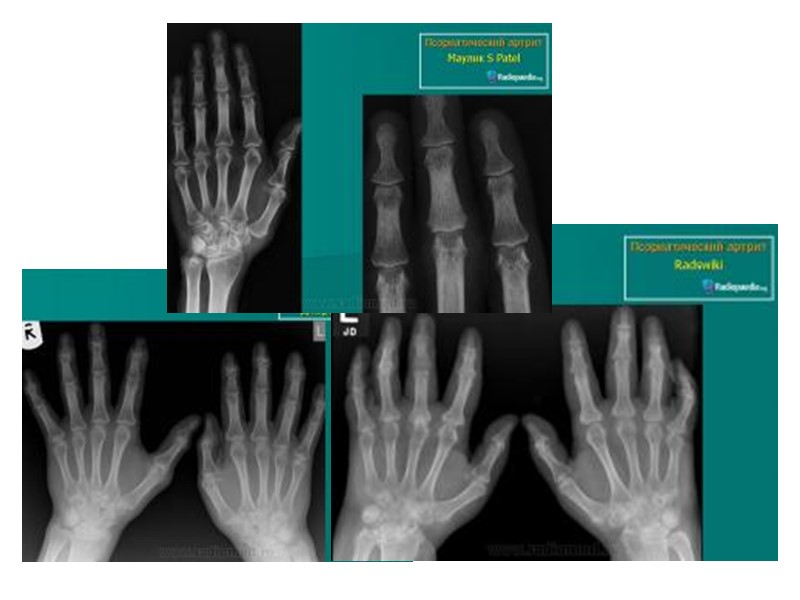

Рентгенологические признаки, помогающие отличить псориатический артрит от других воспалительных ревматических заболеваний суставов: Асимметричность поражения суставов кистей. Артрит на рентгенограммах может быть без околосуставного остеопороза. Изолированное поражение дистальных межфаланговых суставов кистей при отсутствии изменений или небольших изменениях в других мелких суставах кистей. Осевое поражение 3-х суставов одного пальца. Поперечное поражение суставов кистей одного уровня (одностороннее или двухстороннее). Деструкции концевых фаланг (акроостеолиз). Концевое сужение (атрофия) дистальных эпифизов фаланг пальцев рук и пястных костей.

Рентгенологические признаки, помогающие отличить псориатический артрит от других воспалительных ревматических заболеваний суставов (продолжение): Чашеобразная деформация проксимальной части фаланг пальцев кистей вместе с концевым сужением дистальных эпифизов - симптом «карандаш в колпачке» . Костные анкилозы, особенно проксимальных и дистальных межфаланговых суставов кистей. Множественный внутрисуставной остеолиз и деструкции эпифизов костей с разнонаправленными деформациями суставов (мутилирующий артрит). Воспалительные изменения в крестцово-подвздошных суставах -сакроилеиты (обычно двухсторонние асимметричные или односторонние; возможно отсутствие сакроилеита). Изменения в позвоночнике (асимметричные синдесмофиты; паравертебральный оссификат) .

Новая кость сужение суставной щели эрозии Веретенообразная припухлость мягких тканей